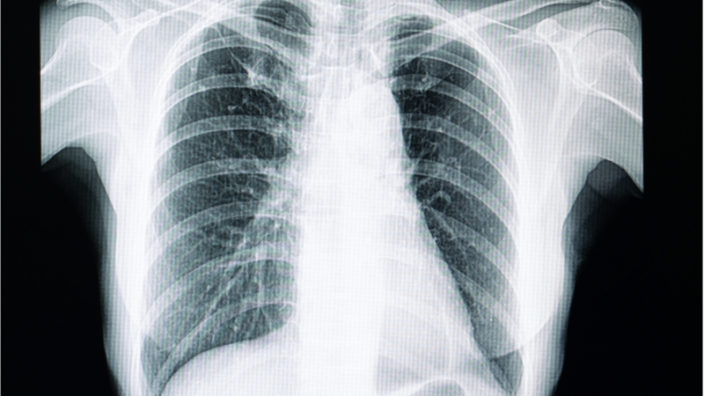

The thymus is a small organ located in the upper part of the chest directly behind the sternum and between the lungs. Before we are even born and through childhood, the thymus is busy producing and maturing T cells, immune cells that patrol the body and destroy invading pathogens. The thymus secretes a hormone known as thymosin, which is needed for the creation and maturation of T cells.